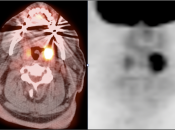

- Any Unilateral Tonsillar Uptake Associated with Hypermetabolic Cervical Nodes:

Clearly, the presence of hypermetabolic cervical nodes dramatically increases the likelihood of malignancy (and the confidence of your reporting).